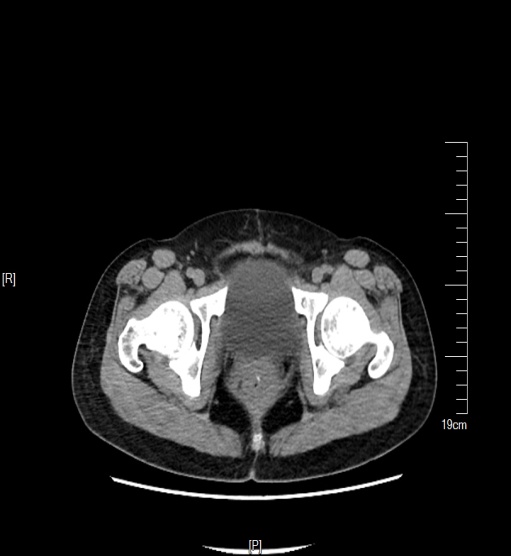

术前CT报告

结果提示:腹盆腔积液,盆腔内不规则软组织密度结节,病灶边界不清,密度不均,子宫和直肠与关系密切,大网膜增厚,局部呈结节样。腹膜另见多处多发结节。腹膜后可见稍大淋巴结。